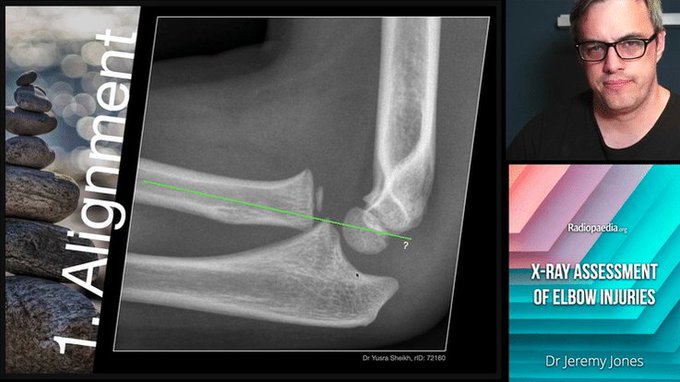

Remember to draw the radiocapitellar line through the unossified radial head and not the shaft. Sage advice from

Terrible triad injury, bad as it sounds. Best to describe the injury rather than use the moniker.

Coronoid process can be hard to see, sometimes quite far away!

Taken from my elbow injuries pathway: https://t.co/6NTLuYkepP